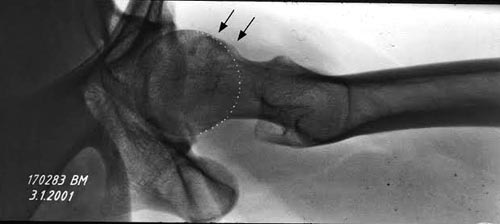

Rg

Спасибо за рентген, который подтверждает нашу догадку, но для окончательного диагноза, кроме обзорного таза, надо добавить боковой false profile снимок, где можно увидеть шейку и определить степень покрытия головки бедра во время нагрузки.

Здесь представлены рентген, боковой, МРТ и клинические снимки деламинации хряща одного того же пациента.